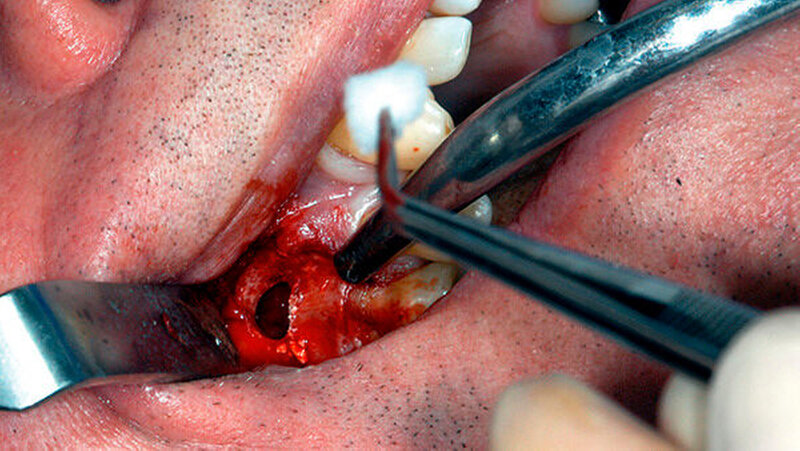

Um die mesiobukkale Wurzel freizulegen, wurde der Knochen darüber entsprechend entfernt (Abbildung 2) und eine Wurzelspitzenresektion an der mesiobukkalen Wurzel Zahn 16 durchgeführt. Das Granulationsgewebe konnte vollständig entfernt werden und wurde für eine histopathologische Untersuchung eingeschickt.

Mit einem ultraschallgetriebenen diamantierten, abgewinkelten Instrument wurden beide Wurzelkanäle der mesiobukkalen Wurzel von retrograd präpariert (Abbildung 3). Das frakturierte Instrument konnte so dargestellt (Abbildung 4) und entfernt werden.